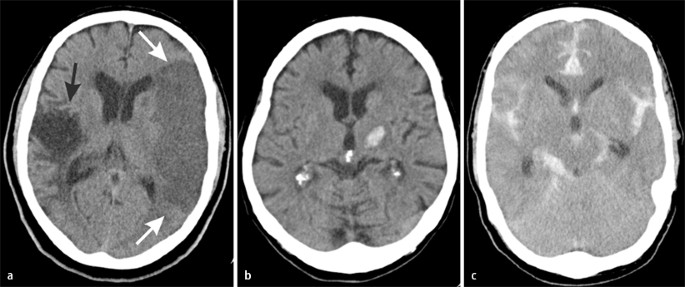

Einen schlaganfall muss für die anschließende therapie herausgefunden werden ob es sich um ein ischämisches oder um ein hämorrhagisches ereignis handelt. Ischämischer schlaganfall ii welearn inwitten. Diese unterscheidung ist am besten mit einem cct möglich. Die skala liefert einblicke in die lokalisation der gefäßläsion korreliert mit dem outcome ischämischer schlaganfälle und identifiziert kandidaten die für eine thrombolytische therapie in frage kommen.

Unsubscribe from welearn inwitten. Der ischämische schlaganfall oder hirninfarkt oder auch weißer schlaganfall ist die häufigste form des schlaganfalls. Auch wenn sich ein ischämischer infarkt erst nach einigen stunden demarkiert ist eine frische blutung sofort zu identifizieren. Mini med studium 19 225 views.

Ursache ist eine als ischämie bezeichnete plötzliche minderdurchblutung des gehirns und damit eine minderversorgung mit sauerstoff und glukose die zur energiegewinnung benötigt werden. Mrt beim akuten ischämischen schlaganfall. Giovanni defilippo hausarzt. Mini med studium mit prim.